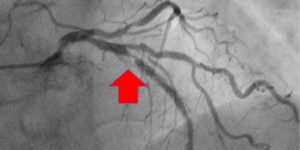

Пример томограмм МРТ сердца и сосудов